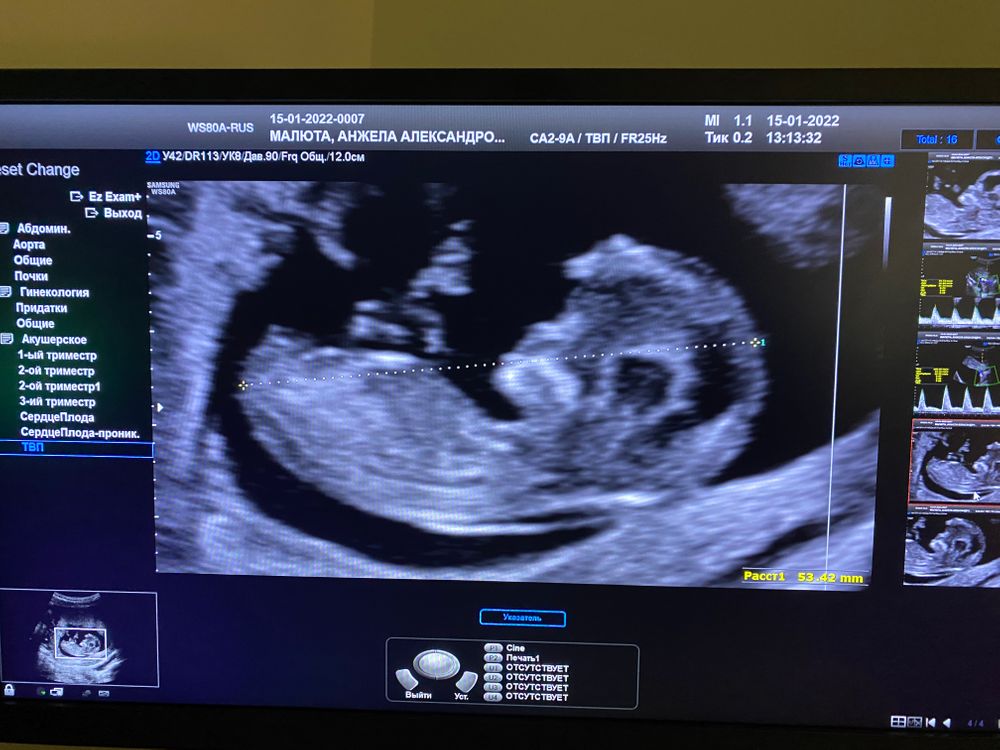

Первое узи ,скрининг )

Результаты: УЗИ, КТГ, доплера, скринингаНу что вот оно самое первое узи и заодно скрининг ,плод ровно на 12 недель )

Очень странное начало этой беременности,была мазня ,кровило ,в четверг были кровотечение и много сгустков,я была настроена на выкидыш или отслойку,но по узи все чисто 🤷🏼♀️Ни гематом ,ни отслоек,единственное киста моя чуть выросла чуть больше 10 см 🤦♀️Так же не понравилась шейка и кровотоки в матке ,поэтому через 2 недели снова на узи ,предположили девочку ,но сказала что через неделю сказала бы точнее ,так как бугорок не выражен вообще)